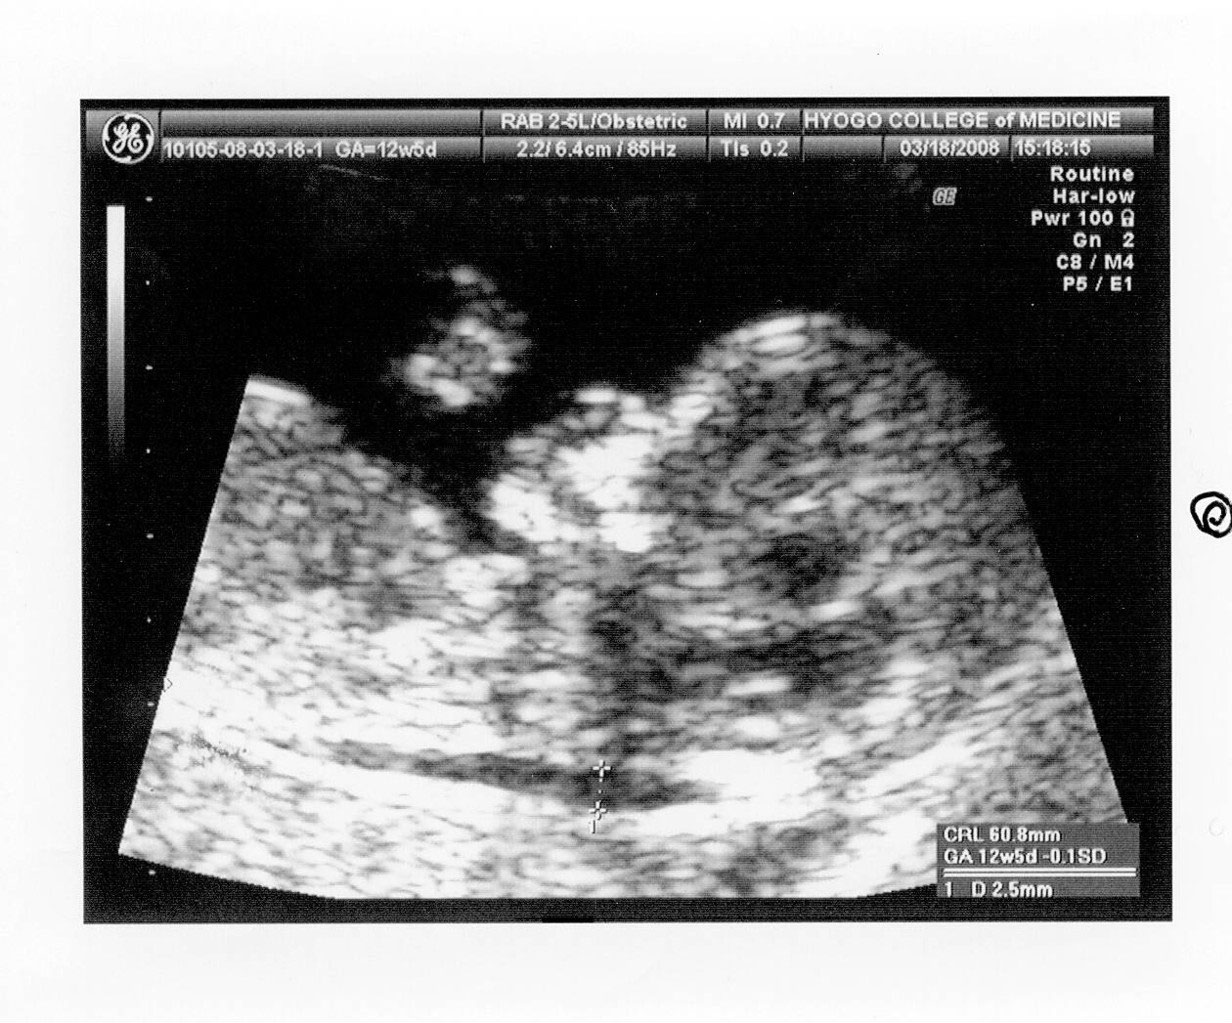

超音波検査 兵庫医科大学病院 出生前診断

02 妊娠初期 胎児の頸部浮腫 Nt 妊娠11 13週でcheck 深谷産婦人科 医学情報

胎児の首の後ろのむくみ 浮腫 Nt とは 妊娠初期 All About

胎児の首の後ろのむくみ 浮腫 Nt とは 妊娠初期 All About